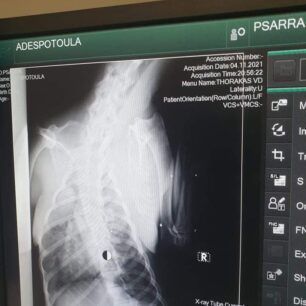

Το ζώο χειρουργήθηκε στις 9 Νοεμβρίου καθώς μεταξύ άλλων είχε και πυομήτρα. Οι ακτινογραφίες, που έβγαλε στην κλινική έδειξαν και τα πολλά σκάγια στο κορμί του – δηλαδή έχει πυροβοληθεί από κυνηγό – καθώς και το κάταγμα κνήμης και περόνης στο πόδι, το οποίο αντιμετωπίστηκε με νάρθηκα, αλλά και ο υγρό στον πνεύμονα (το όποιο αφαιρέθηκε με παρακέντηση). Είχε επίσης και εσωτερική αιμορραγία στην κοιλιακή χώρα.